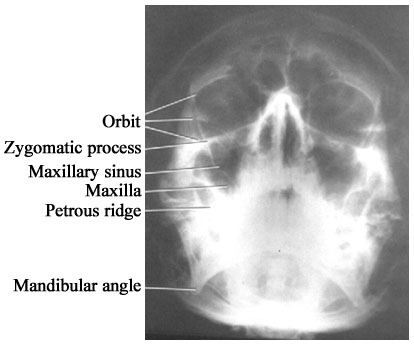

1.6.  Water's view (Parietoacanthial projection)

ใช้ดู facial bones และ paranasal sinuses  ดังรูป sk.6  การถ่ายดู  paranasal sinuses ใช้ upright position และ coned-down views ใน Water's, inclined PA และ lateral

รูป sk.6 Water's view เห็น orbit, maxillae, zygomatic arches ชัดเจน